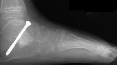

of the left foot. The procedure consisted of :

- subtalar arthrodesis with autograft bone graft and screw fixation

- closing wedge calcaneocuboid arthrodesis with open pinning

- reduction and open pinning of the talonavicular joint

- midfoot soft tissue release of the talonavicular, calcaneocuboid and

subtalar joints

Post operatively, the patient was placed in a long leg cast. Preliminary

results show satisfactory reduction of the talonavicular joint, correction

of hindfoot valgus, dorsiflexion of the talus on the calcaneus, and correction

of forefoot adduction immediately post op.